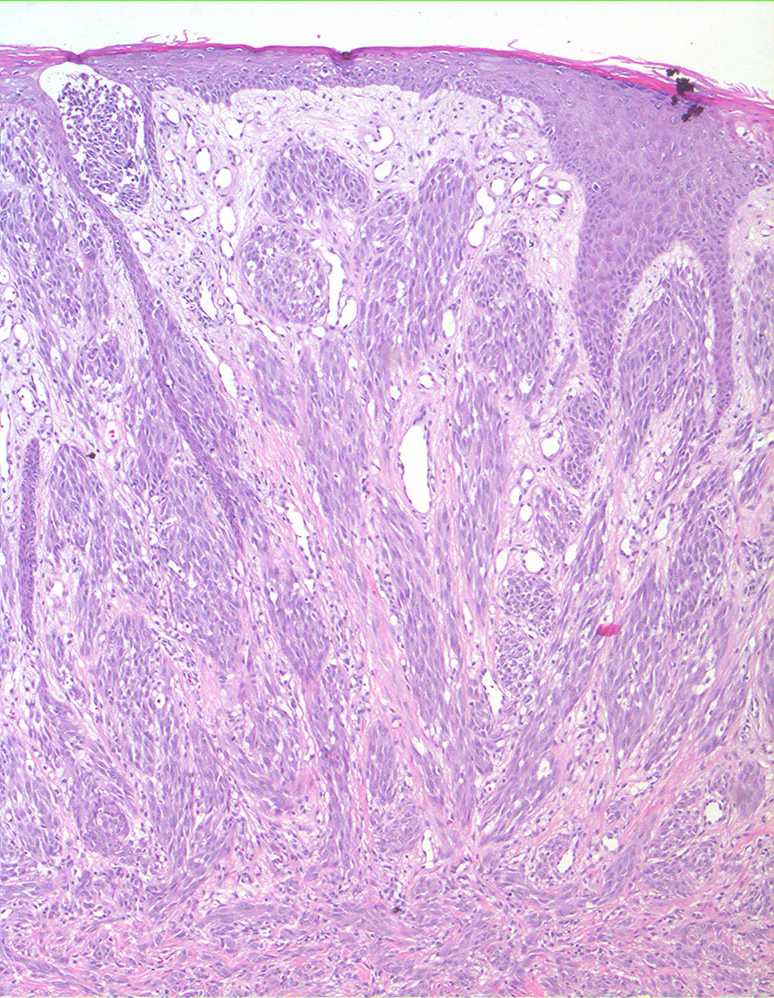

Spitz naevus (juvenile melanoma) = وحمة سبيتز _الميلانوم الفتوي